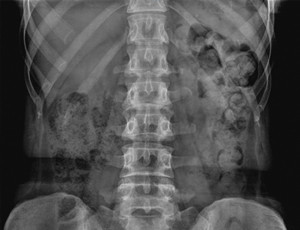

• также может понадобиться рентген органов брюшной полости;

imageЧаще всего проводят рентгенографию брюшной полости, с помощью которой выявляется наличие газов и высота стояния диафрагмы. Чтобы оценить количество газов применяют быстрое введение в кишечник аргона. При этом удается измерить объем вытесняемых аргоном кишечных газов. Кроме того, применяют следующие методы диагностики: